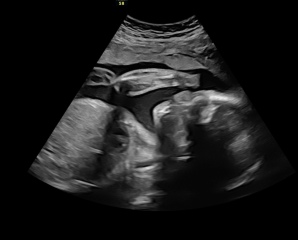

I had a private scan yesterday at 26+1, baby was not playing nicely, kept moving everywhere, wouldn’t face the scanner and at one point totally turned their back 😂

It was just a standard scan so the lady changed to 4D so we got to see the face 🥰

It was wonderful being able to see the movement and feel it at the same time ❤️